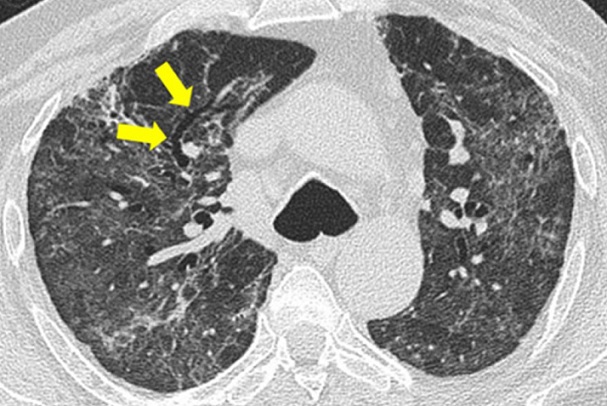

Three weeks after being discharged he returned to hospital with sharp chest pain. Surprisingly, he had no fever cough breathing difficulty or signs of serious infection. New CT scans revealed a large cavity filled with air and fluid in his left lung. A week later another cavity appeared in the right lung.

Despite alarming images of lung damage the patient remained stable with normal oxygen levels and low inflammation markers. Because no infection was found doctors stopped antibiotics and chose close monitoring instead.